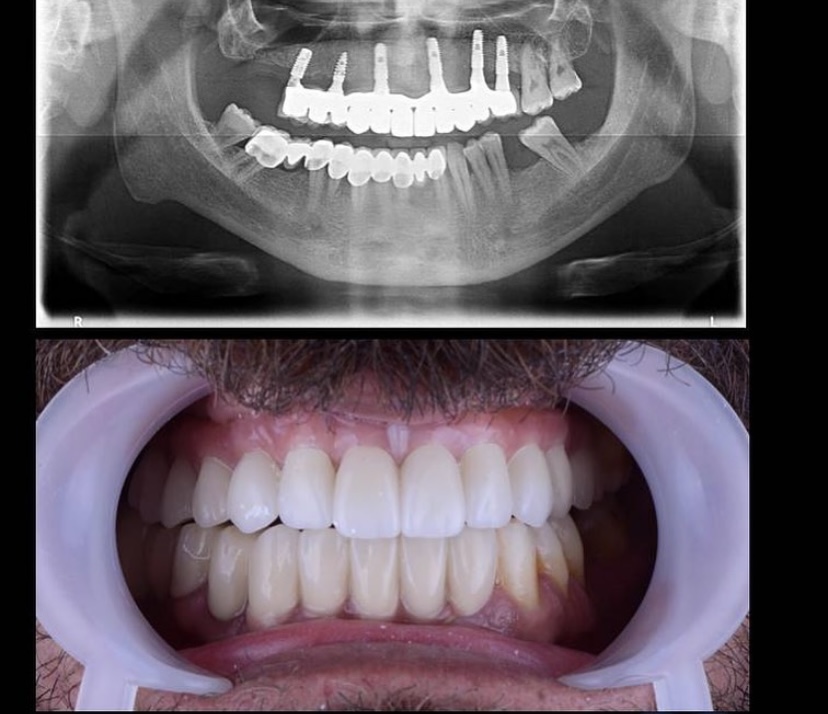

Öncesi̇-Sonrası Resi̇mler

Galeri Öncesi̇-Sonrası Resi̇mler